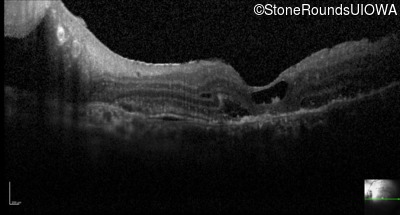

Optical Coherence Tomography - Right - 20/50 +2

Exemplar / OCT Stack